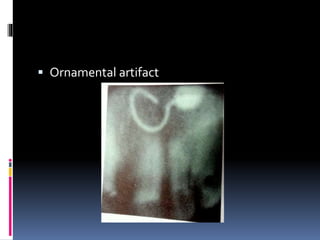

 Ornamental artifact